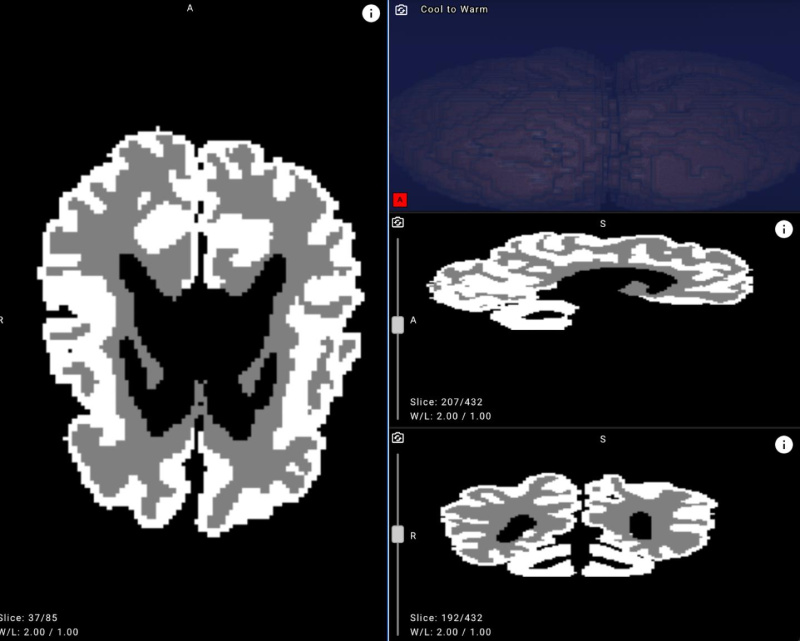

Example of an MRI brain image with white matter and gray matter masks applied after neural network processing.

To bridge this gap, Yandex researchers collaborated with medical experts to create new annotations, design a dedicated neural network architecture, and run a series of machine learning experiments. The resulting model achieved over 90% accuracy in distinguishing gray and white matter in infant brains on internal evaluation data, demonstrating its potential for clinical use.

- Improve accuracy and objectivity. With over 90% accuracy, the model highlights outlines and quantifies the ratio of gray to white matter in an infant’s brain.